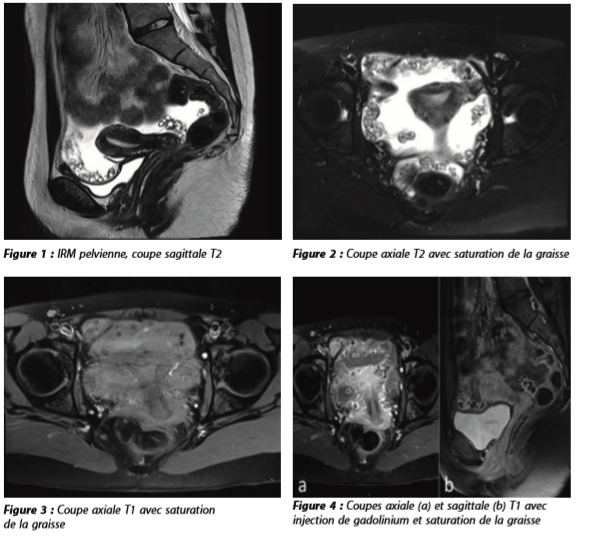

Une patiente de 15 ans, vivant dans l'est de la France, à la campagne, est adressée en échographie pédiatrique du CHU de Besançon pour mise en évidence lors d'une échographie abdomino-pelvienne réalisée en externe d'un épanchement péritonéal avec lésions péritonéales pelviennes kystiques d'allure tumorale et hypertrophie de l'ovaire droit. Ses symptômes sont des douleurs abdominales diffuses et modérées, évoluant depuis 6 mois et ayant notamment débutées 1 mois après un traumatisme abdominal de l'hypochondre droit. La patiente est en excellent état général.

Une IRM pelvienne est ensuite demandée, que vous réalisiez.

Interprétez l'IRM : vous suspectez un diagnostic. Quel examen d'imagerie complémentaire faites-vous ?